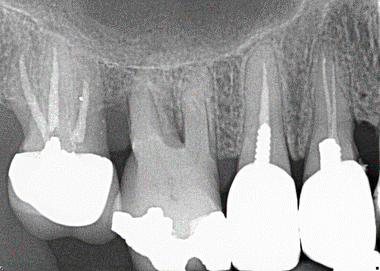

4. Select ONE OR MORE correct answers)

Which of the following may complicate the extraction of tooth 1.7?